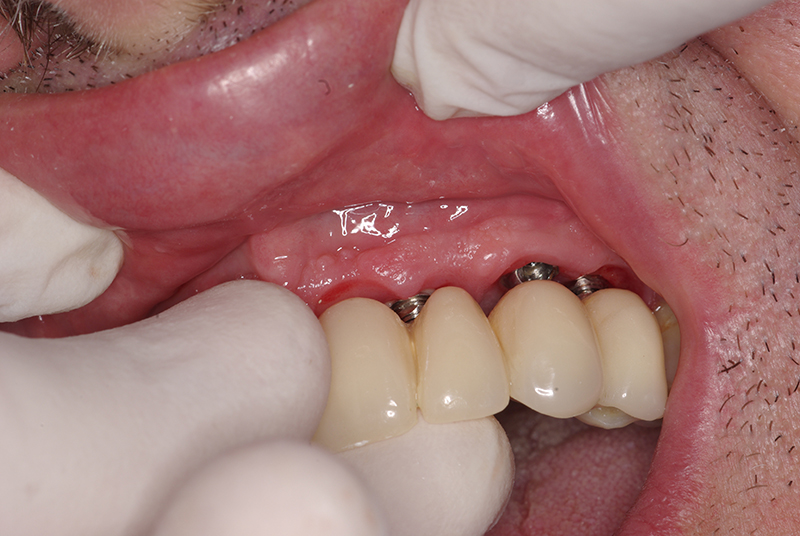

Na Clínica Pontes Odontologia, somos referência em implantes dentários em Fortaleza, oferecendo tratamentos de alta qualidade e tecnologia de ponta. Os implantes dentários são estruturas de titânio posicionadas cirurgicamente no osso maxilar ou mandibular para substituir as raízes dos dentes ausentes. Essa técnica permite a fixação de próteses personalizadas, restaurando a função mastigatória, a estética e a autoestima dos nossos pacientes.

Utilizamos a tecnologia CAD CAM, um sistema avançado que possibilita a confecção precisa das próteses dentárias diretamente sobre os implantes. Esse método inovador garante um ajuste perfeito, um resultado estético superior e proporciona muito mais conforto e durabilidade. Com o CAD CAM, nossos pacientes contam com um processo mais rápido e previsível para alcançar o sorriso desejado.